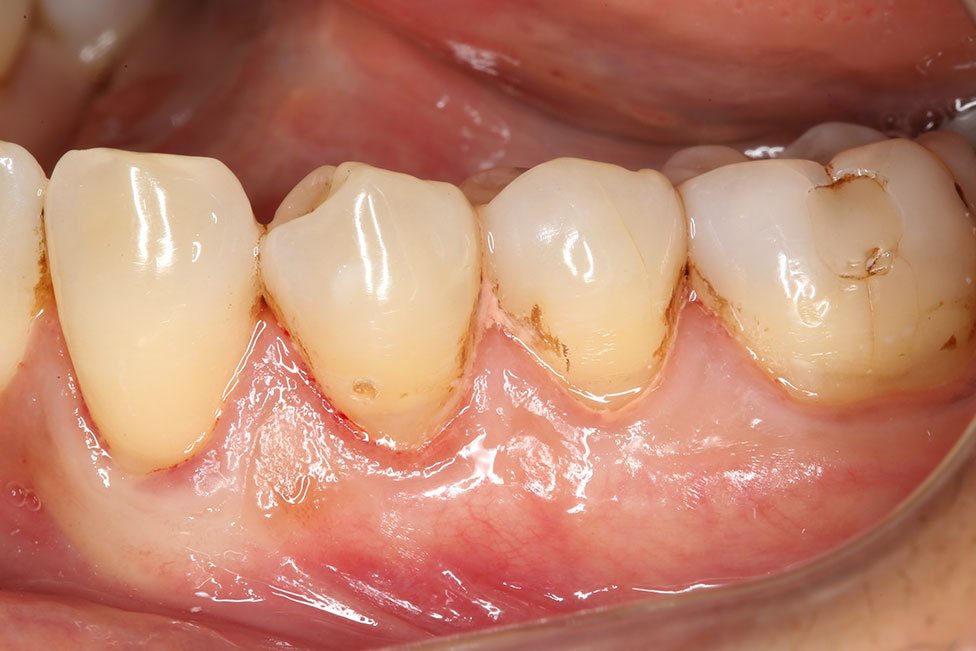

Gallery - Receding Gums

Case 23

Before After